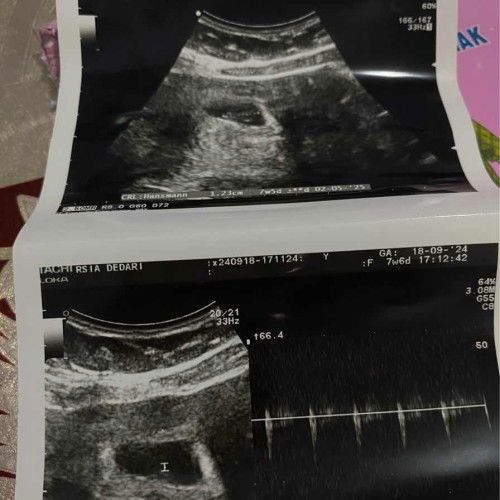

7w6d hsil usg nya sdh ada kantung dan janinnya, bahagianya awal pertama kali dengar detak jantungnya. Semoga sehat dan lancar smpai lahiran nanti🤲🏻😇